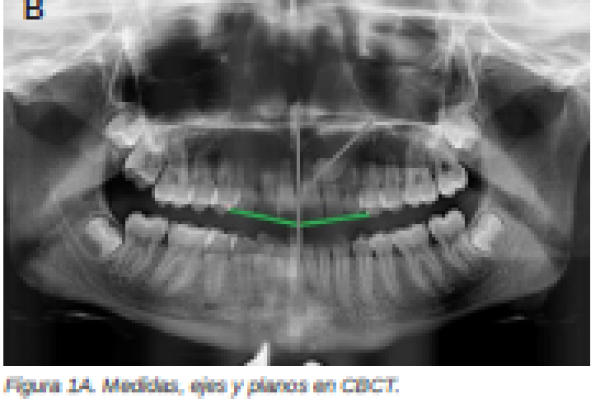

Diagnóstico radiográfico de los caninos maxilares incluidos. Comparación entre dos y tres dimensiones